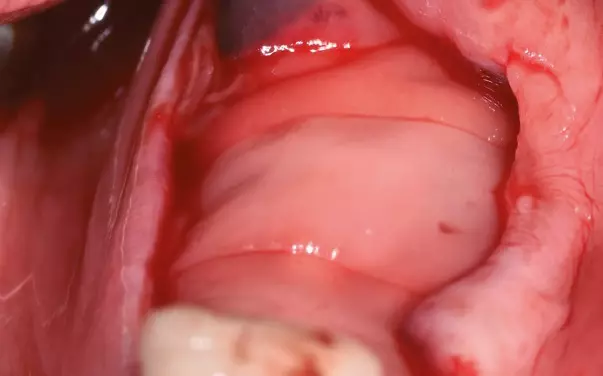

Um einer Resorption des Knochens um die Extraktionsalveole vorzubeugen, wurde die Alveole mit einem intraoperativ individualisiertem bovinen Block DBBM-C (Deproteinized bovine bone Matrix-Collagen, Geistlich BioOss-Collagen, Geistlich Biomaterials) aufgefüllt. Im Anschluss erfolgte eine Adaptionsnaht (Abb. 2). Die postoperative Phase verlief ohne Besonderheiten, sodass die Nähte nach sieben Tagen entfernt werden konnten. Beim Kontrolltermin nach acht Wochen zeigte sich die Wunde vollständig und reizlos abgeheilt (Abb. 3).